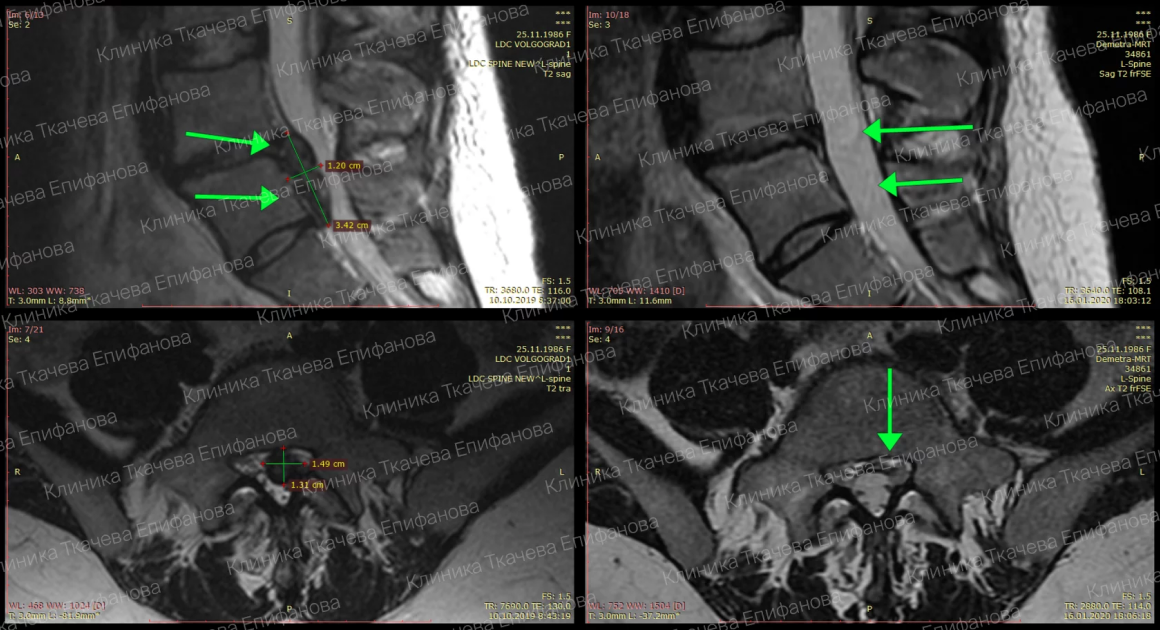

Слева МРТ до лечения, грыжа диска L5-L6 1.2 на 3,4 сантиметра. Октябрь 2019.

Справа МРТ после лечения – грыжа полностью растворилась, то есть наступила резорбция. Январь 2020.